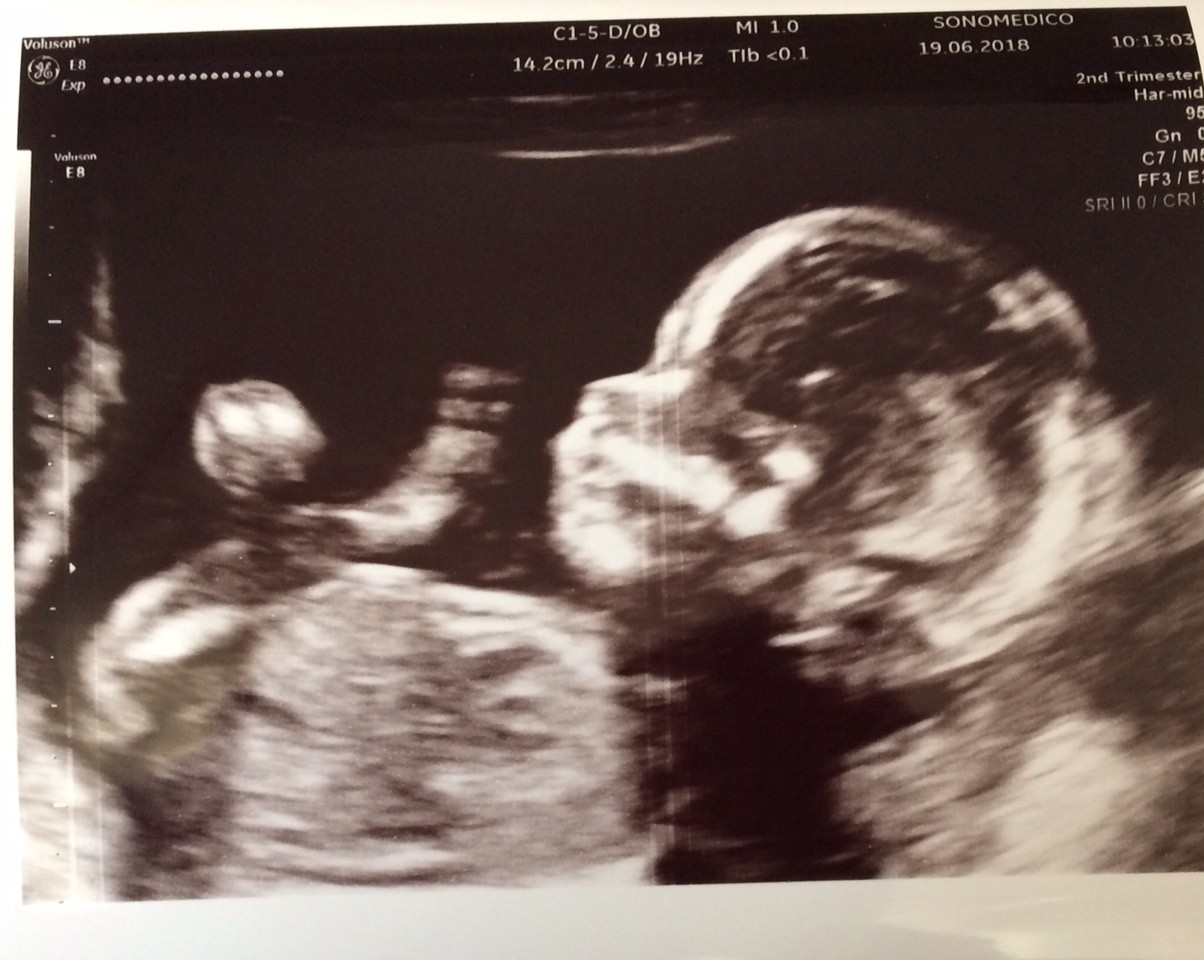

A to nasze niestety słabe, rączki i nóżki były cały czas w ruchu.

To dobrze, że jest w ruchu, kręci się i wierciA to nasze niestety słabe, rączki i nóżki były cały czas w ruchu.